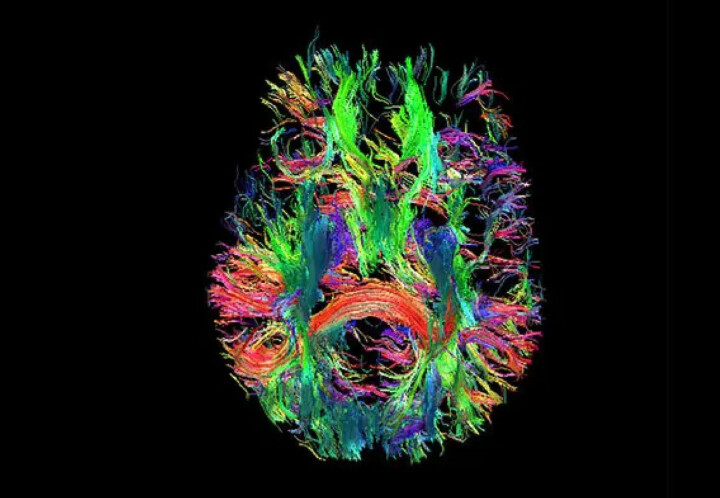

Cinquant'anni dopo la prima immagine scattata con la tecnologia MRI, i ricercatori della Duke University, in collaborazione con scienziati di diverse università, sono riusciti a creare un'immagine MRI che è 64 milioni di volte più chiara della tecnologia convenzionale.

La nuova tecnologia cattura i dati in tre dimensioni e crea i cosiddetti “voxel”, cioè pixel in tre dimensioni, dove la dimensione di ciascun elemento costitutivo dell'immagine è di soli 5 micron. Questo, tra l'altro, può aiutarci a capire cosa succede nel cervello affetto dalla malattia di Alzheimer.

Con l'aiuto di un magnete da 9,4 Tesla, fino a tre o quattro volte più potente dei magneti odierni, e la potenza di calcolo di un supercomputer più piccolo, i ricercatori sono stati in grado di catturare una sequenza di immagini di un intero cervello di topo, di cui vediamo una sezione Qui.